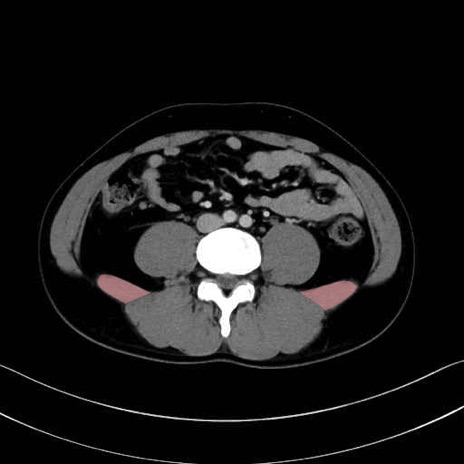

腰方形筋(quadratus lumborum muscle)のCT画像の解剖

腰方形筋 (Quadratus lumborum)

大腰筋 (Psoas major)